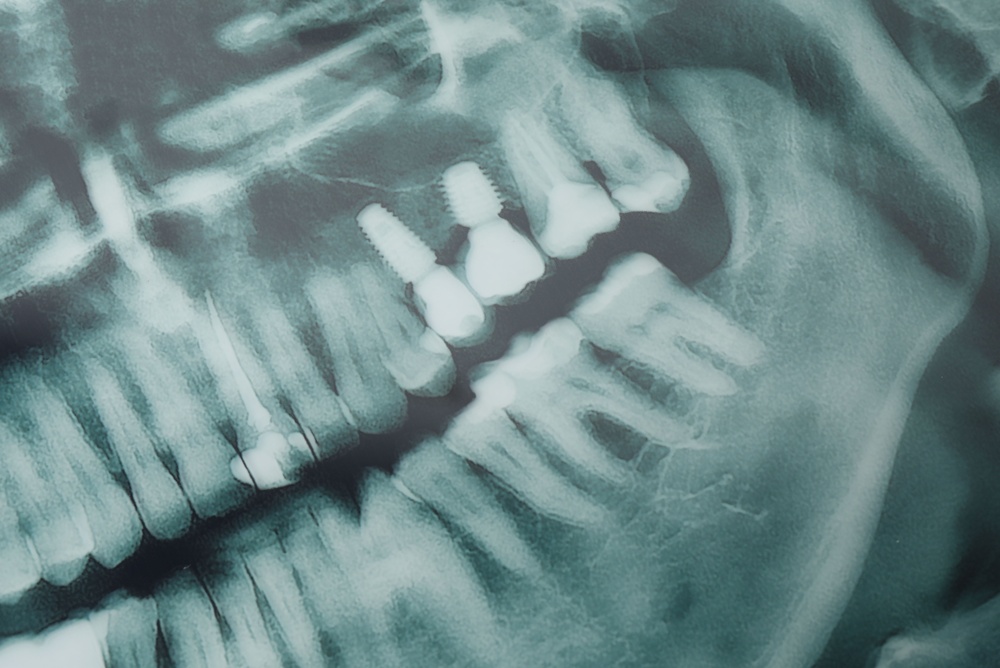

The fixture is the part placed in bone. Most fixtures are titanium and may have surface treatments—like roughening or coating—to speed bone attachment. Some systems offer zirconia fixtures for metal-free options.